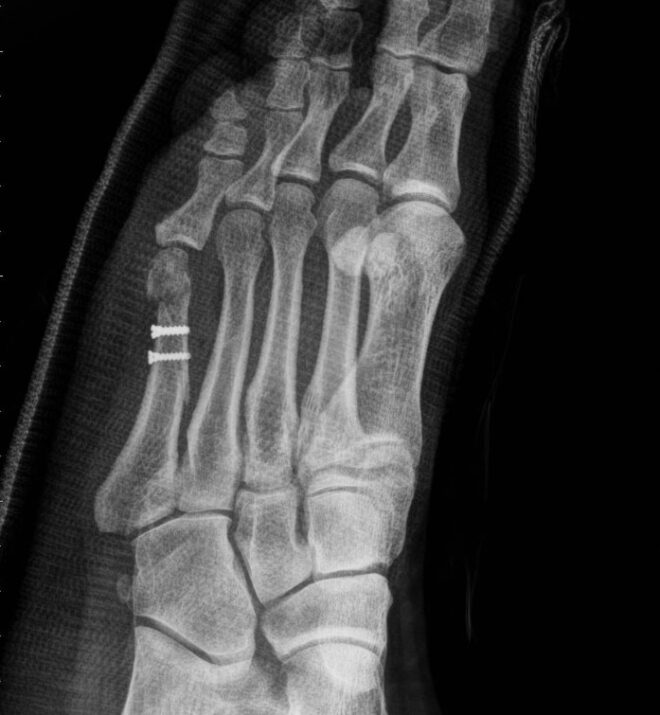

درمان شکستگی شافت متاتارس پنجم “رقصنده باله” معمولاً بدون عمل جراحی انجام میشود. درمان شامل استراحت نسبی و زمان برای بهبودی شکستگی است. به طور معمول ، برای بیماران یک گچ کوتاه گرفته میشود و برای چند هفته اول ، آنها باید راهپیمایی خود را به میزان قابل توجهی محدود کنند و ممکن است به عصا (شکل ۳) احتیاج داشته باشند.

جراحي به ندرت مورد نياز است اما در صورت جابجايي كامل قطعات شكستگي يا عدم بهبودي در درمان غير جراحي ممكن است لازم باشد. در این موارد ، قطعات استخوان با پیچ و یا یک صفحه دوباره جابجایی و تثبیت می شوند.